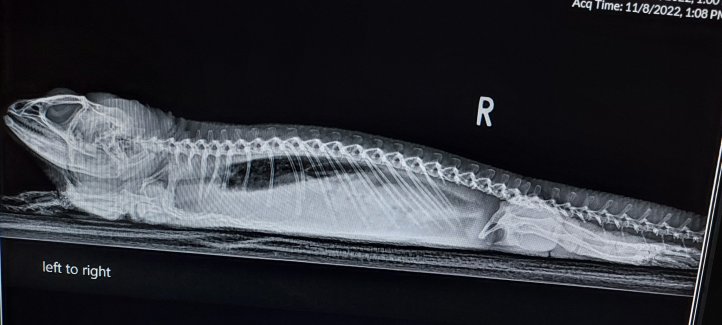

The doctor enters the room. He discusses my teeth, an option is surgery, but he fears when the yellow is scraped, bone will be visible, maybe Mommy just keeps me as comfortable as possible, that Benzocaine can numb my gums. She translates that as a form of hospice. He said overall, my phosphorus level is good, calcium is on the low side of good, and he proceeds to discuss my X-rays.

The black image is my lung. Do you see that subtle white haze overlapping the edge? It’s fluid. The doctor said this is indicative of a failing liver or a liver tumor.